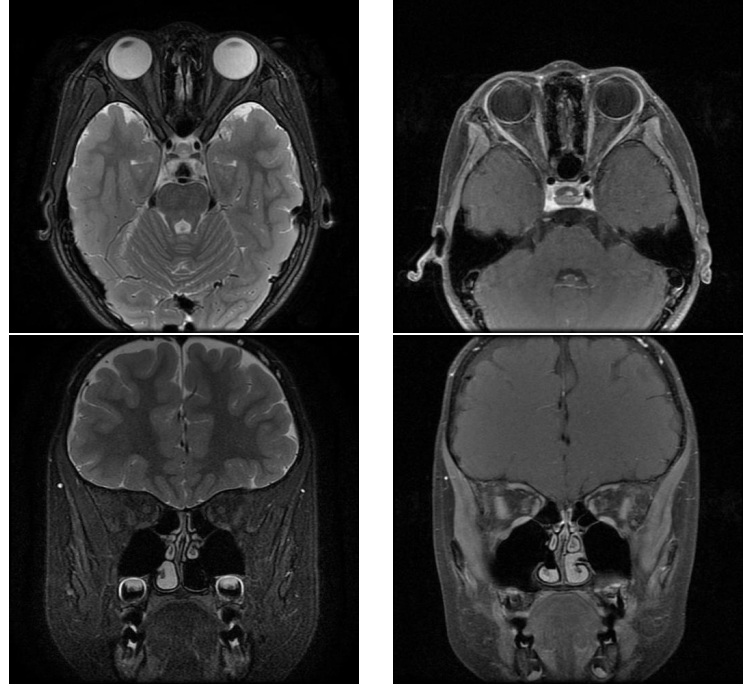

查体:视力:右眼1.0,左眼指数/20 cm(矫正不增),双眼结膜无充血,角膜透明,瞳孔圆,直径约3 mm,对光反射正常,晶状体透明,眼底视乳头色淡红,边界清,C/D约0.3,视网膜血管走行大致正常,无出血、渗出,黄斑区未见异常。眼压:右眼 15 mmHg(1 mmHg=0.133 kPa),左眼13 mmHg。为了明确患儿发病原因,完善下列相关检查:血常规、血生化、免疫学指标未见明显异常。血清水通道蛋白4(aquaporin 4,AQP4)抗体、髓鞘少突胶质细胞糖蛋白(myelin oligodendrocyte glycoprotein,MOG)抗体阴性。闪光视觉诱发电位(flash visual evoked potential,FVEP)(图1):左眼P2波峰时值相对右眼稍延迟,右眼波幅相对左眼降低。闪光视网膜电流图(flash electroretinogram,FERG):双眼FERG五项反应未见明显异常。视盘+黄斑光学相干层析成像(optical coherence tomography,OCT)(图2):未见明显异常。眼眶MRI平扫+增强:未见视神经长T2及T1增强信号(图3)。相对性传入性瞳孔障碍(relative afferent pupillary defect,RAPD)阴性。

图 3 眼眶 MRI 平扫 + 增强:双眼未见视神经长 T2 及 T1 增强信号

Figure 3 Orbital MRI scan with enhanced enhancement showed that there was no long T2 and T1 enhanced signal of the optic nerve in both eyes